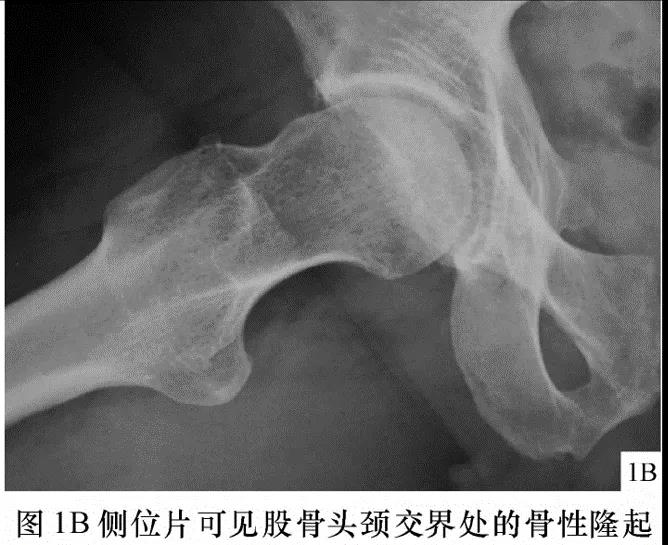

FAI影像学检查前后位片:可见股骨头不同程度的手枪柄样畸形侧位片: 观股骨头颈交界处骨性隆起;CE角﹥40°;髋臼后倾畸形;股骨颈的囊性变

FAI:齿轮型(cam-type )影像:股骨头、颈间的凹陷不足,可伴局部的骨质增生、硬化、囊变部位:前外股骨头、颈交界区